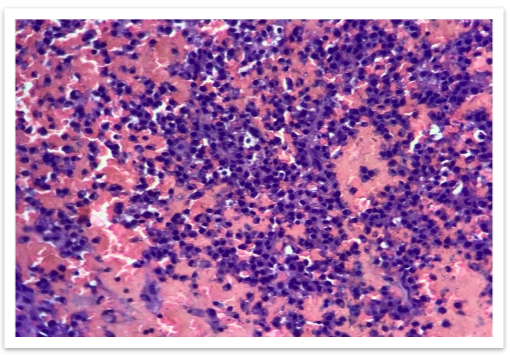

The MRI findings showed multiple focal altered signal intensity lesions (Figure 2). A bone biopsy was performed, and histopathological examination revealed the presence of plasma cells.

Immunohistochemistry showed plasmacytoid cells are positive for CD 138 (Figure 6). The patient was diagnosed with non-secretory multiple myeloma.